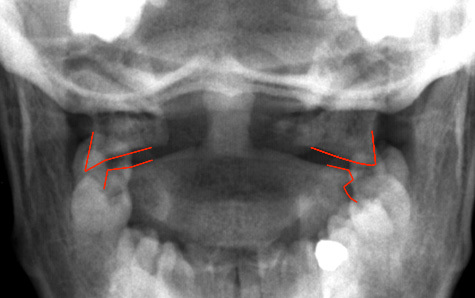

4th or 5th MCP

Bar room facture

2nd or 3rd MCP

fracture

Boxer’s fracture